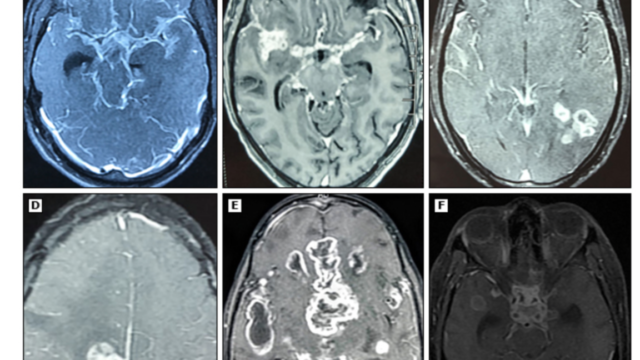

クリプトコッカス髄膜炎